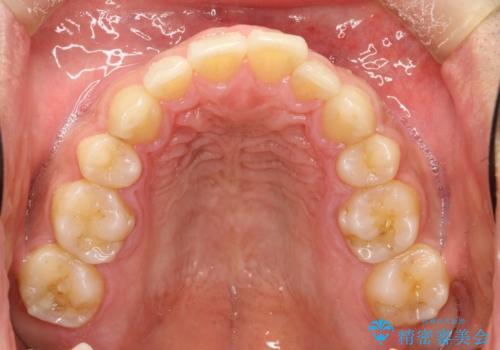

マウスピース矯正にて、下の歯はIPR(歯と歯の間を削る)を入れることでガタガタの改善、咬み合わせの深さも改善をはかる治療計画をたてました。

歯と歯の間を削って隙間を作って矯正をしています。